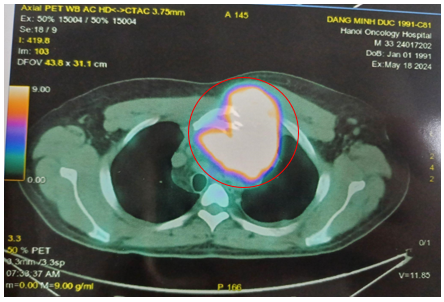

-         Hình ảnh chụp PET/CT đánh giá giai đoạn trước điều trị (tháng 5/2024)

·        Hạch nền cổ, thượng đòn 2 bên, lớn nhất ~ 28x18mm (SUVmax: 10.47).

·        Khối lớn ở trung thất trước, lệch trái kích thước ~84x109x90mm, phá hủy xương ức,cung trước xương sườn 3 trái, thành ngực trước trái, xâm lấn quai động mạch chủ (SUVmax: 17.88).

·        Vài hạch trung thất, lớn nhất 14x17mm (SUVmax: 3.17). Hạch rốn gan, hạch bẹn. Tăng nhẹ chuyển hóa FDG lan tỏa ở hệ thống xương.

Hình 2: Hình ảnh tăng chuyển hoá FDG ở nhiều vị trí khối lớn ở trung thất trước, hạch cả ở trên và dưới cơ hoành, tăng FDG lan tỏa hệ thống xương.

Hình 3: Khối lớn ở trung thất trước, lệch trái kích thước ~84x109x90mm, phá hủy xương ức

Nhận xét: Sau 06 chu kỳ điều trị, khối trước xương ức giảm kích thước (từ 109x90mm còn 57x45 mm, trước điều trị SUVmax: 17,88 -> sau điều trị SUVmax 5,79). Hạch cổ, hạch thượng đòn, hạch bẹn, hạch rốn gan không còn nhìn thấy trên phim PET/CT, không tăng chuyển hoá FDG -> PET/CT sau 6 chu kỳ hóa trị: Đáp ứng một phần (PR) theo tiêu chuẩn Lugano 2014.